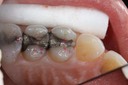

Kyle Chock #19 amalgam removal